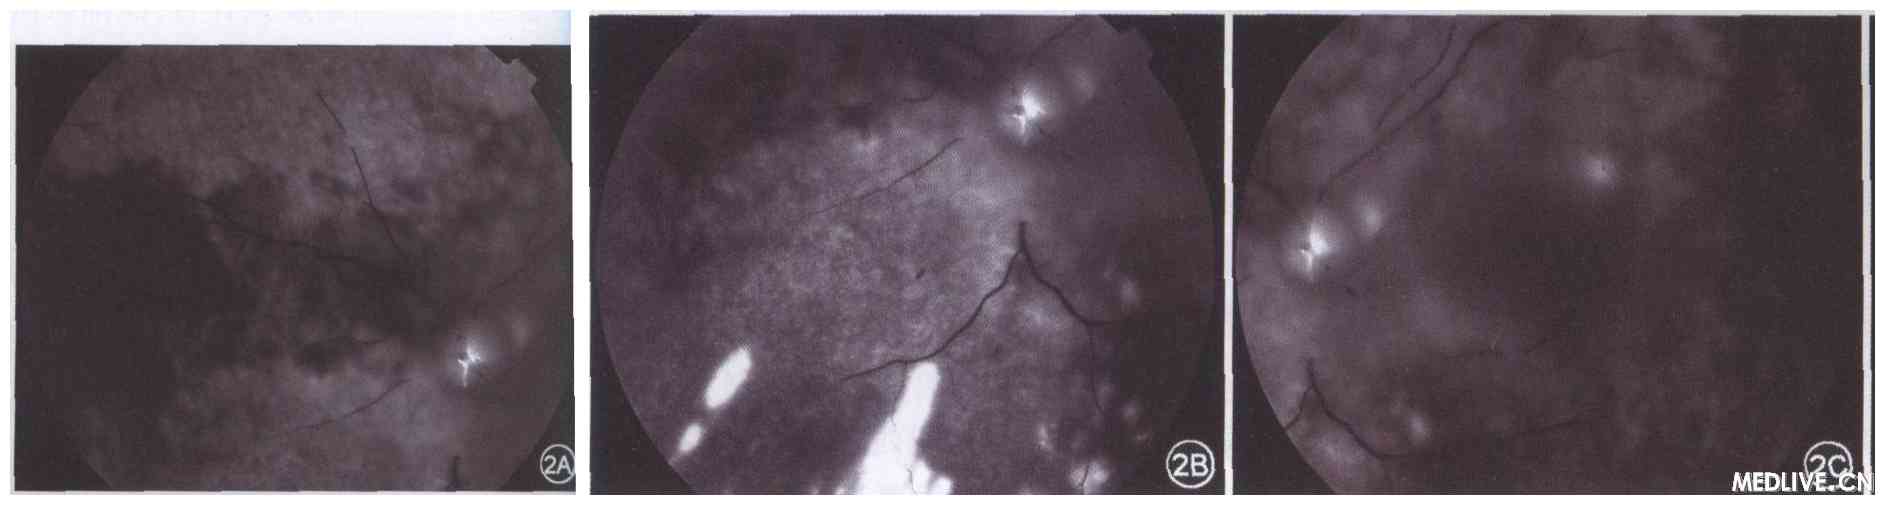

荧光素眼底血管造影(图2):左眼12.6 s时,颞上方可见脉络膜循环,视乳头低荧光;60. 03 s时,视乳头鼻侧脉络膜循环仍未见;动、静脉无充盈,后极部及黄斑区视网膜高荧光,血管淹没其中;晚期视乳头高荧光;右眼未见异常荧光;诊断:左眼动脉阻塞。

图2左眼动脉阻塞患者荧光素眼底血管造影图像

2A示左眼造影60.03 s时,视乳头鼻侧脉络膜循环未见,动、静脉无充盈;

2B和2C示左眼造影晚期,后极部和黄斑区视网膜呈现高荧光,血管淹没其中